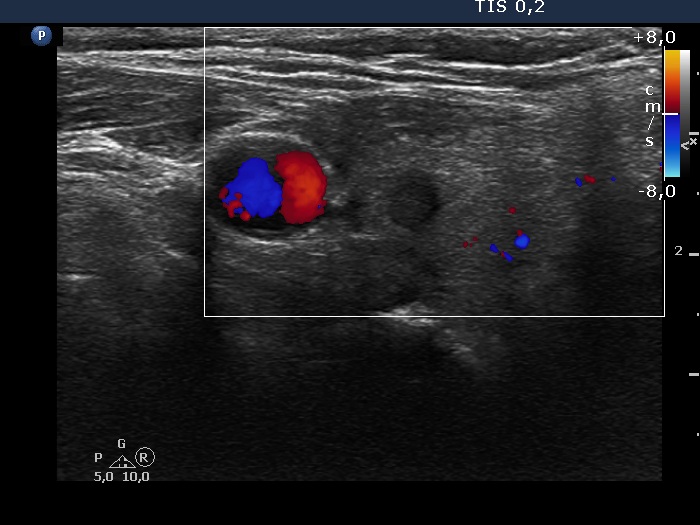

Ultrasonography. The thyroid was minimally hypoechoic and has several discrete lesions. A hypoechoic one in the left lobe showed both taller-than-wide and taller-than-long shape. There was a dominantly solid nodule in the lower part of the right lobe. There was a hypoechoic nodule in the upper, ventromedial part of the left lobe. This was the only lesion which was larger than 1 cm. This had a bit elongated hyperechoic figure.